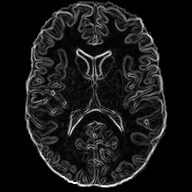

Diffeomorphic deformable multi-modal image registration is a challenging task which aims to bring images acquired by different modalities to the same coordinate space and at the same time to preserve the topology and the invertibility of the transformation. Recent research has focused on leveraging deep learning approaches for this task as these have been shown to achieve competitive registration accuracy while being computationally more efficient than traditional iterative registration methods. In this work, we propose a simple yet effective unsupervised deep learning-based multi-modal image registration approach that benefits from auxiliary information coming from the gradient magnitude of the image, i.e. the image edges, during the training. The intuition behind this is that image locations with a strong gradient are assumed to denote a transition of tissues, which are locations of high information value able to act as a geometry constraint. The task is similar to using segmentation maps to drive the training, but the edge maps are easier and faster to acquire and do not require annotations. We evaluate our approach in the context of registering multi-modal (T1w to T2w) magnetic resonance (MR) brain images of different subjects using three different loss functions that are said to assist multi-modal registration, showing that in all cases the auxiliary information leads to better results without compromising the runtime.

In this paper, we propose a novel unsupervised multi-modal image registration approach to tackle the problem of registering images of different subjects (inter-subject) acquired by two different imaging modalities (T1w, T2w MR images). We are integrating ideas from the work of Pluim et al. [10] that combines mutual information with a term based on the magnitude and direction of the image gradients to rigidly register 3D MR, CT and PET images, the work of Qin et al. [11] that uses segmentation maps as auxiliary information to guide the task of motion estimation and the work of Zhe Xu at al. [12] that performs unsupervised multimodal CT-MR image registration leveraging the deformation fields estimated from a branch aiming to align the original fixed and moving images and a branch aiming to align the corresponding gradient intensity maps.

Similarly, we propose to make use of the edge maps extracted the images, as a complementary signal, to aid the training of registration network. The main assumption is that since the anatomy depicted by the two modalities is very similar, the edge maps can serve as a geometrical constraint. At the same time,

the edges are less \saymodality dependent, a property that is very useful in the case of multi-modal registration due to the fact that we do not have to deal with the complicated intensity relationship between the modalities. This simple, yet, effective technique shows that the edge signal can be beneficial for multi-modal image registration.

2.1 Edge Maps

As stated above, the edge maps extracted from multi-modal images can be a useful auxiliary information to guide multi-modal image registration. Specifically, the edge map of a 2D (but easily extensible to 3D) image can be easily obtained by calculating the central differences between adjacent pixels.

We decided to only use the gradient magnitude because it is sufficient to depict the underlying geometry and discard the information relating to the edge direction. The part of the network that handles the edge maps is more sensitive in capturing the structural dependencies between the two images, rather than the complex intensity relationships, and hence serves as a spatial constraint assisting the task of image registration. In practice, the edge maps are given as input to an encoder which adopts the same architecture as the one that handles the images.

We evaluate our work on the task of inter-subject brain MRI registration on T1w-T2w images. For this purpose, we decided to use the Cambridge Centre for Ageing and Neuroscience (CamCAN) dataset [20], [21]. The dataset consist T1w and T2w MR 3D volumetric images of 310 subjects, with isotropic spatial resolution. In our work we only use 2D slicse of the volumetric image cropped to the size of . Although this work could directly be transferred in 3D, we use 2D images as a proof-of-concept, due to the large computational requirements when using 3D images. After affine alignment to a common MNI space using ANTs [22], the images are skull-stripped using ROBEX [23] and bias-field corrected using the N4 algorithm in SimpleITK [24]. For evaluation, we also acquired the segmentation of 138 cortical and sub-cortical structures (grouped into 5 groups) automatically using MALPEM [25].